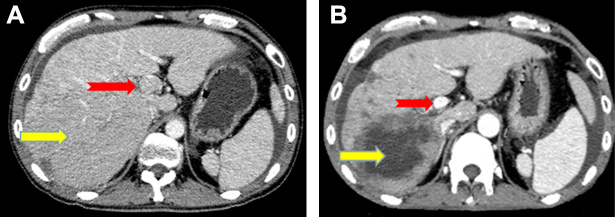

All patients had complete follow-up records and all the responses were therefore evaluable. Tumor response was assessed using mRECIST criteria. Treatment efficacy was evaluated 1 month after the start of treatment. The overall objective response and disease-control rates of the combined treatment were 63.15% and 84.21%, respectively, including 12 partial responses, four cases of stable disease, and three cases of progressive disease. The median progression-free survival was 8.1 months (Figure 1) and the median overall survival was 11.9 months (Figure 2). In terms of PVTT response rates, two patients (10.53%) achieved partial responses, 15 patients (78.94%) had stable disease, and two patients (10.53%) had progressive disease 1 month after therapy. The objective response rate of PVTT was 10.53% and the disease-control rate was 89.47%. Examples of follow-up CT images in patients who achieved a partial response 1 month after combined apatinib with TACE therapy are shown in Figure 3.

Figure 3: Image of a 48-year-old man with hepatocellular carcinoma and PVTT who showed a partial response after combined apatinib and TACE treatment. Contrast-enhanced CT at diagnosis showed a 134 mm diameter hepatocellular carcinoma nodule (yellow arrow) and multiple small metastatic lesions located in the liver, together with PVTT in the left and main portal vein (red arrow). CT images 1 month after diagnosis showed intrahepatic lesions in numerous non-enhanced areas (yellow arrow) and almost complete absence of PVTT without definite enhancement (red arrow).